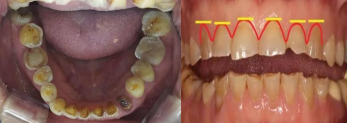

在工作中经常会见到一些病人,明明牙齿上没有龋洞,却自述咬东西没有力气,有酸酸的感觉,这个时候如果你仔细观察会发现,他们的牙齿往往失去了正常的形态,牙被磨平,牙面发黄,牙齿变短这些可能会导致他们咀嚼效率降低

这些问题便是牙齿重度磨耗的一些表现及危害,那么牙齿重度磨耗的病因,危害具体都有那些呢,又该如何防治呢?

首先,什么是磨耗?磨耗是指在咀嚼过程中,由于牙面与牙面之间,或牙面与食物之间的摩擦,使牙齿硬组织自然消耗的生理现象。牙齿的磨耗随着年龄增长而逐渐明显,多发生在牙齿,它是人体一种增龄性生理反应,具有协调牙周组织和咀嚼功能的作用。而重度磨耗则是由于咬合关系异常如缺牙,单侧咀嚼,咬合过紧,夜磨牙,嗑瓜子等不良生活习惯引起的病理性磨损和年龄增长的结果。